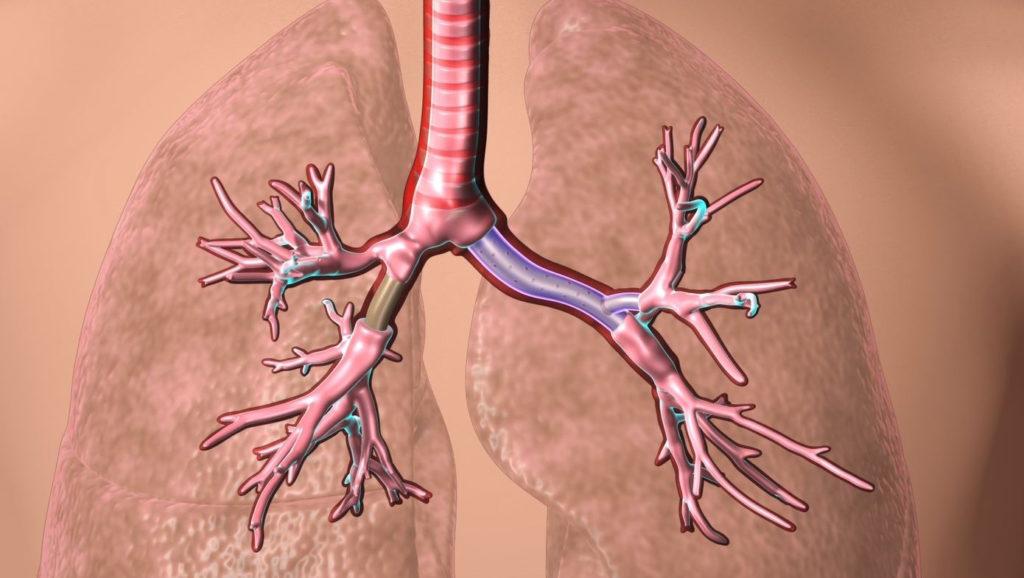

There are two primary types of stents used in lung procedures: expandable metal stents and silicone stents. Expandable metal stents, often referred to as esophageal stents, are the most widely used. These self-expanding stent structures are typically constructed from nitinol, a nickel-titanium alloy that allows for compression and subsequent expansion. Metal stents have mesh-like configurations...